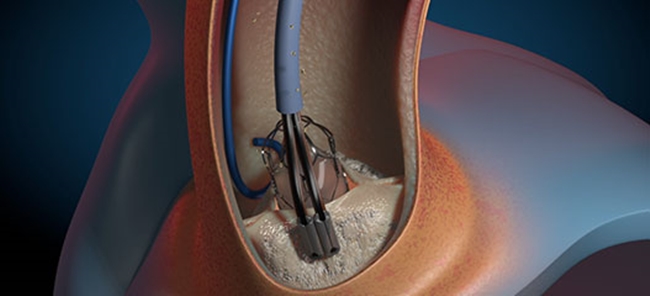

트랜스 카테터는 대동맥 판막의 석회화를 파편화하기 위해 피에조 유도 페어 피치 기술을 사용한다(사진. Aortic Lab)

경피적 대동맥판막 치환술(TAVI) 절차를 연기하기 위해 AorticLab은 초음파 히스토트립시를 위한 트랜스 카테터 변연절제술 솔루션을 개발했다. 대동맥 판막의 석회화를 부드럽게 파편화해 기능을 회복하도록 설계됐다. 장치 내에서 피에조 트랜스듀서는 두 개의 다른 주파수에서 초음파를 발생시켜 조직과 판막에서 석회화를 분해하는 강력한 캐비테이션 효과를 생성한다.

AorticLab의 R&D 프로젝트 리더인 Enrico Fermi는 “PI Ceramic의 고품질, 고성능 피에조 트랜스듀서를 사용하여 낮은 에너지 파동을 생성해 중요한 조직을 손상시키지 않고 매우 효과적으로 치료할 수 있다”라고 밝혔다.